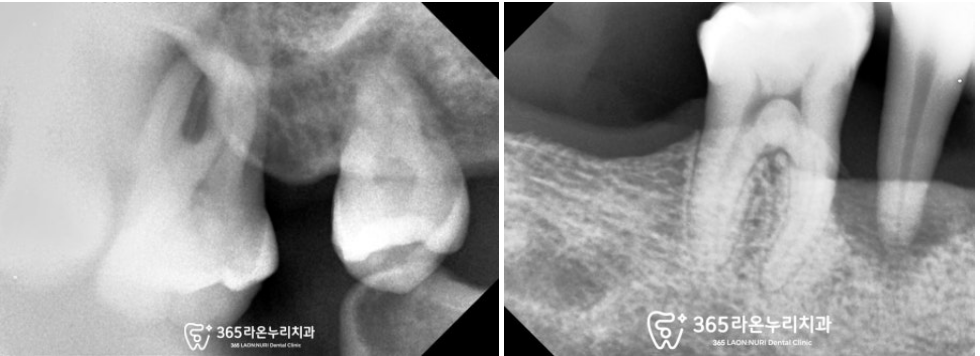

파노라마는 구강 전체가 나오는 사진이라

치근단 사진을 찍어 한 번 더 살펴보았습니다.

보이는 것처럼 뿌리를 잡아주는

주변의 잇몸뼈가 녹아

까맣게 보이죠?

이렇게 되면 우리우리한 통증과 함께

이가 흔들리게 됩니다.